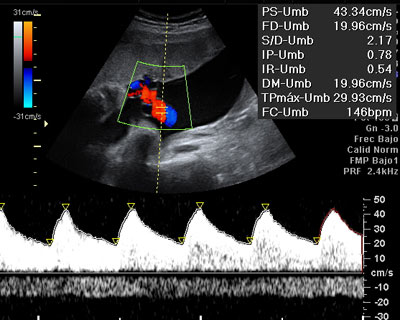

Ecografía del tercer trimestre: Doppler del cordón umbilical

La ecografía Doppler en el tercer trimestre de embarazo permite conocer cómo es la flujo sanguíneo en el cordón umbilical. Si resulta normal quiere decir que el feto recibe la cantidad de oxígeno necesario para su correcto desarrollo.

Ecografía Doppler normal del cordón umbilical

La ecografía Doppler nos ayuda a valorar si el estado de salud fetal es adecuado.